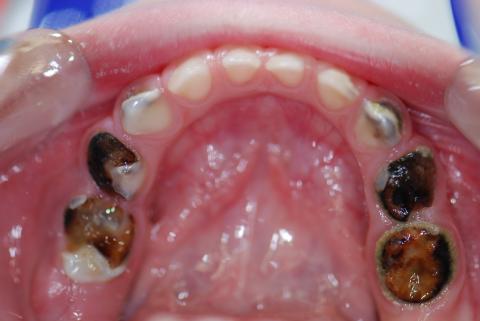

Upon zooming in at 100%, the molar region (likely third molar or second molar area) shows grayish-black necrotic tissue, possibly indicating infection or tissue death. There is yellowish exudate or pus, a clear sign of acute infection. The gum tissue around the infected site appears inflamed. The adjacent tooth structure is partially covered by infected tissue with visible gum swelling. This can be a sign of pericoronitis, abscess, or developing dry socket (if post-extraction).